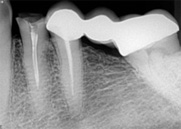

antes depois